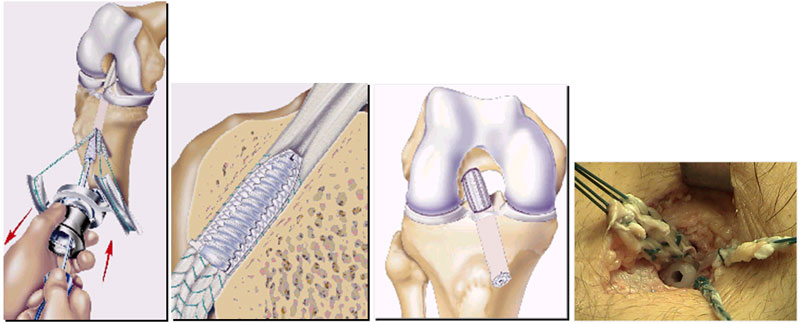

Tratamento

Atualmente, a indicação de tratamento para indivíduos fisicamente ativos que apresentam instabilidade anterior do joelho é a reconstrução ligamentar com enxertos. Os enxertos mais utilizados são os tendões da pata de ganso (semitendinoso e grácil) e o tendão patelar.

A reconstrução do LCA com tendões flexores (grácil e semitendinoso) é uma técnica que apresenta menor morbidade, pós-operatório menos doloroso e melhor estética, por não envolver um acesso anterior no joelho. Funcionalmente, os enxertos mencionados são equivalentes e têm respaldo na literatura.

Os pacientes são orientados a mobilizar e apoiar precocemente o membro inferior acometido, com acompanhamento de fisioterapeuta e educador físico. Geralmente, são liberados para retornar às atividades físicas de contato após 6 meses.